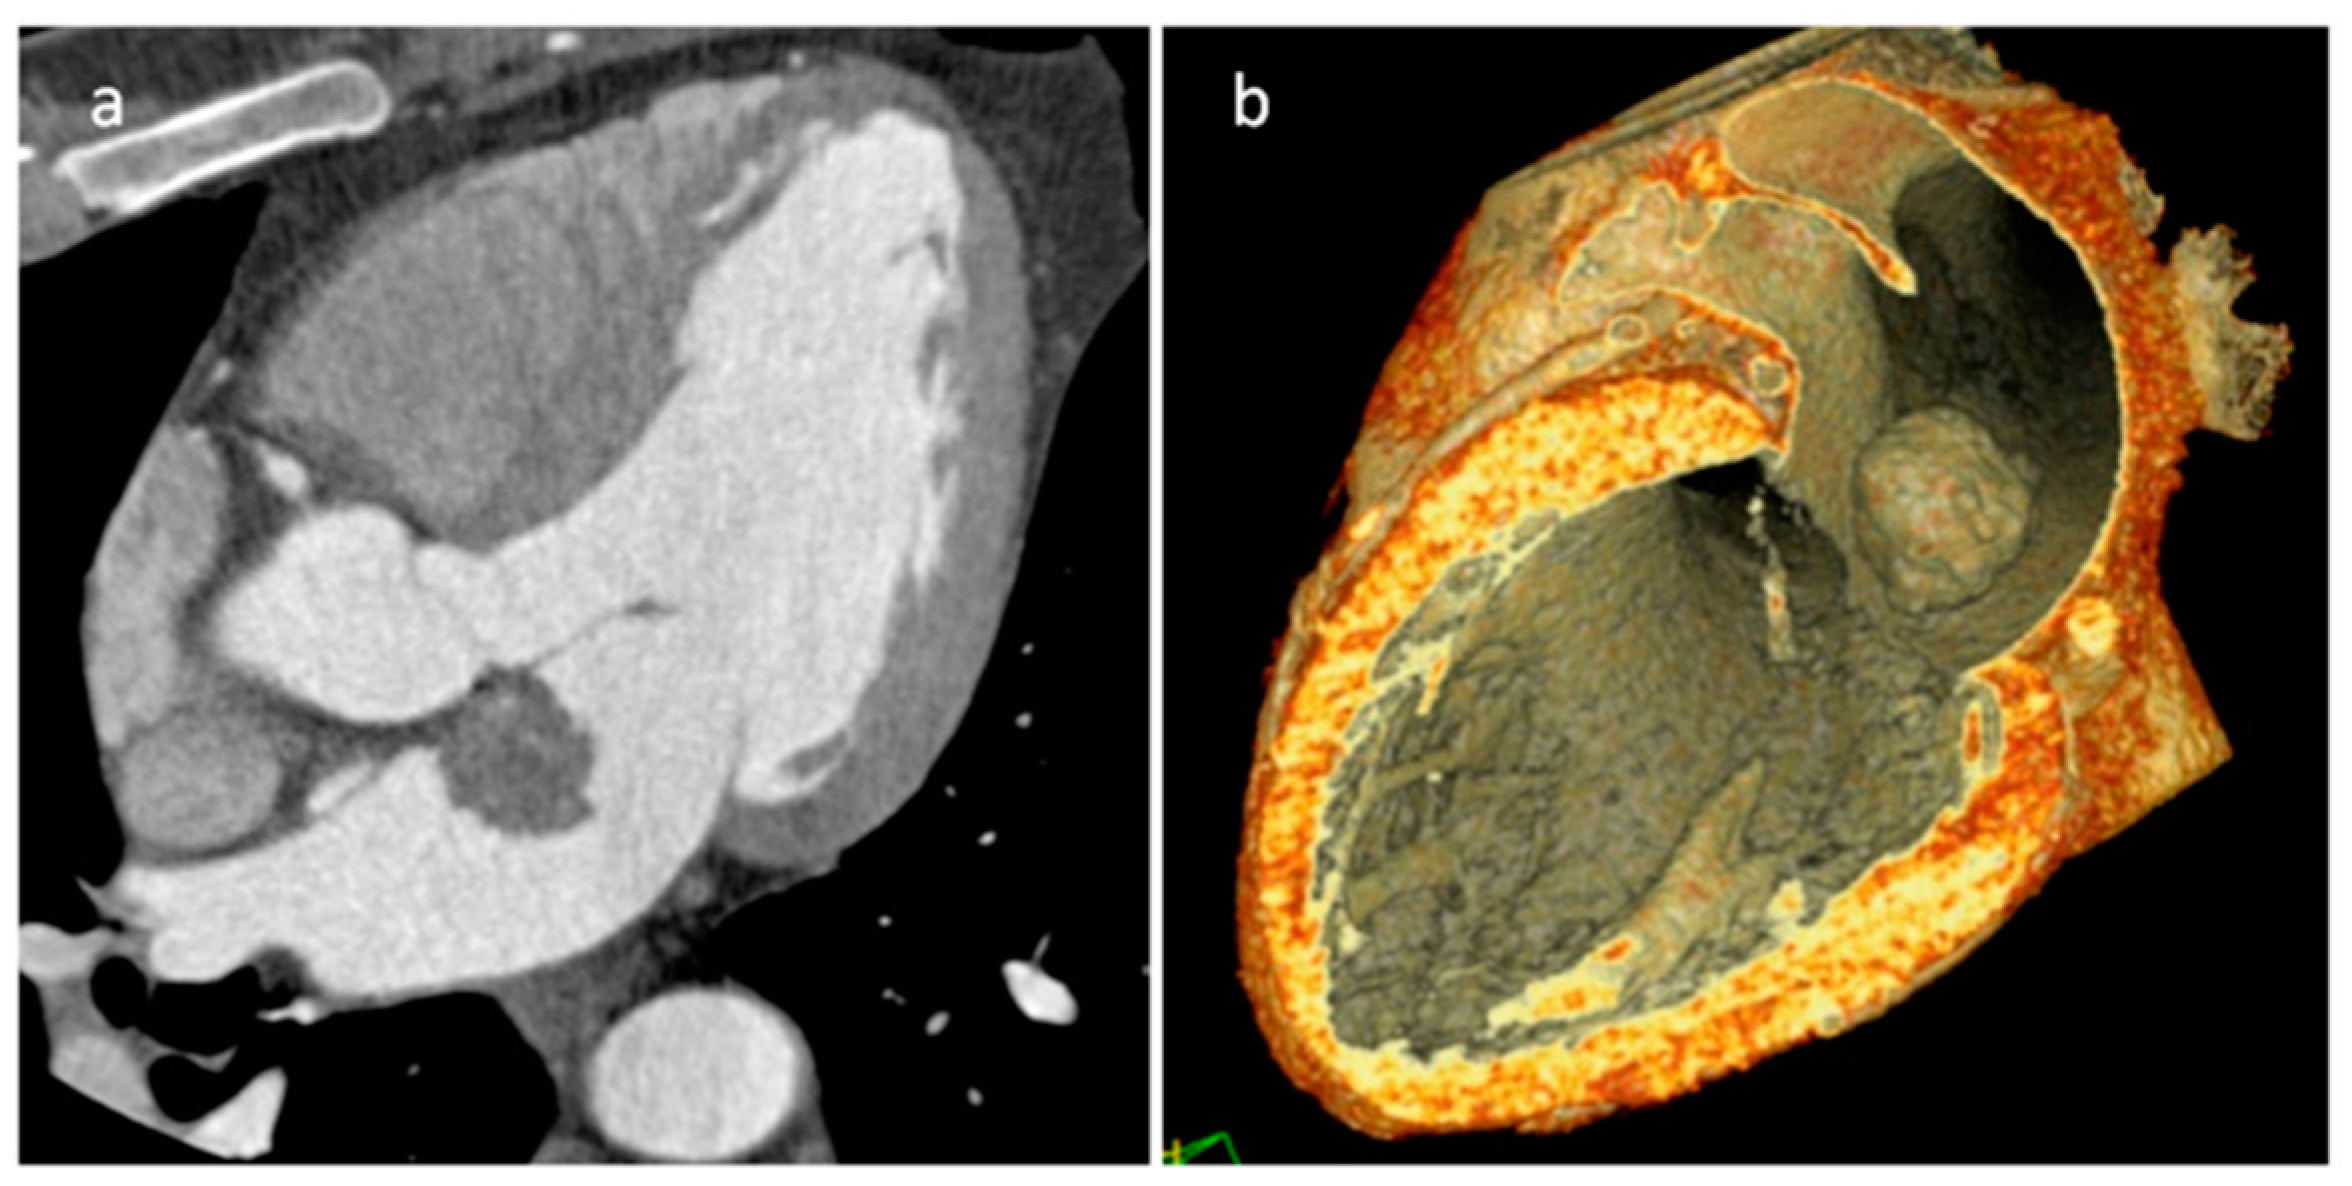

5.2. Primary Cardiac Sarcomas

| Angiosarcoma | Early and middle adulthood, Li-Fraumeni Sd | RA near AV sulcus, pericardium | Constitutional symptoms, heart failure, pericardial effusion | Vascular nature; hemorrhage and necrosis. Lung, liver and brain metastasis. | Iso-hyperechogenic and irregular mass, often as a nonmobile, broad-based, endocardial neoplasm with myocardial extension. Pericardial effusion | low-attenuation, irregular, intracavitary mass is often shown, pericardial thickening with effusion, heterogeneous enhancement | Heterogeneous Iso-hyper T1w, heterogeneous-hyper T2w, marked and heterogeneous enhancement and LGE. Perfusion imaging in the arterial phase shows immediate and strong enhancement |